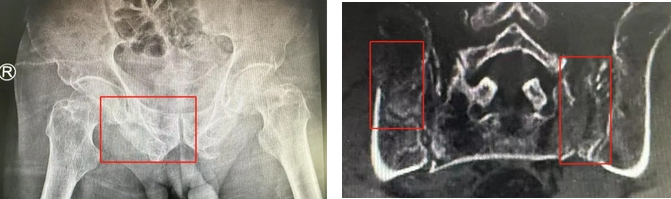

术前影像学显示,患者的左侧骶骨骨折,右侧耻骨骨折、髂骨骨折,骨盆骨折分型为C型,老年脆性骨盆骨折分型为IV型,是极度不稳定型的前环骨折和双侧后环骨折。所幸没有明显的骨盆出血或内脏损伤的表现。

无影灯下,智能骨科团队将患者示踪器安放在左侧髂前上棘,使用术中三维影像设备获取骨盆的三维图像,扫描结果传输至机器人导航系统,完成螺钉置入的位置和走形,并在机器人的引导下分别置入4枚通道螺钉。置入后再次进行CT扫描验证,证实导针精确置入。